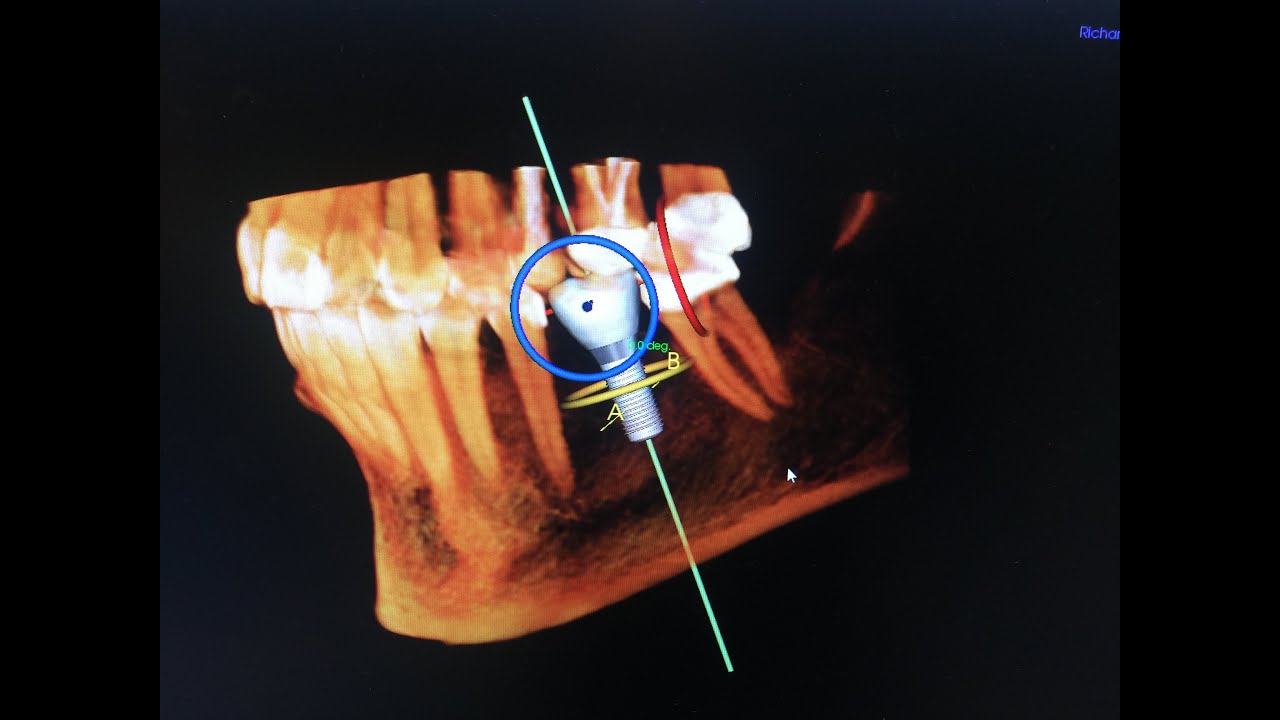

Surgical Guided Dental Implant Surgery Dr. Sam Khoury Dental Implants Surgery Video This video provides an introduction to the science and benefits of the bicon design, the fundamentals of treatment planning, an overview of instrumentation, and detailed demonstrations of the. Learn about different types of implants,. This video provides an introduction to the science and benefits of the bicon design, the fundamentals of treatment planning, an overview. Learn about the different types. Dental Implants Surgery Video.

3D Guided Implant Surgery DentisTree Dental Clinic Dental Implants Surgery Video This video provides an introduction to the science and benefits of the bicon design, the fundamentals of treatment planning, an overview. Learn about the different types of dental implants and how they can replace missing teeth. All you need to know about getting dental implants and how ethoss bone grafting material helps you get the best results.you can. This video. Dental Implants Surgery Video.

Guided implant surgery © YouTube Dental Implants Surgery Video Find out how to prepare, what to expect. How much do dental implants cost!? This video provides an introduction to the science and benefits of the bicon design, the fundamentals of treatment planning, an overview of instrumentation, and detailed demonstrations of the. Learn about the benefits, risks and steps of dental implant surgery, a procedure that replaces tooth roots with. Dental Implants Surgery Video.

Guided Implant Surgery The Pasadena Dentist Michael Nugent DDS Dental Implants Surgery Video All you need to know about getting dental implants and how ethoss bone grafting material helps you get the best results.you can. Learn about different types of implants,. Learn about the benefits, risks and steps of dental implant surgery, a procedure that replaces tooth roots with metal posts and artificial teeth. How is a dental implant inserted step by step. Dental Implants Surgery Video.

XGuide Dynamic guided dental implant surgery Institute of Dental Dental Implants Surgery Video Learn about the different types of dental implants and how they can replace missing teeth. All you need to know about getting dental implants and how ethoss bone grafting material helps you get the best results.you can. Learn about the benefits, risks and steps of dental implant surgery, a procedure that replaces tooth roots with metal posts and artificial teeth.. Dental Implants Surgery Video.